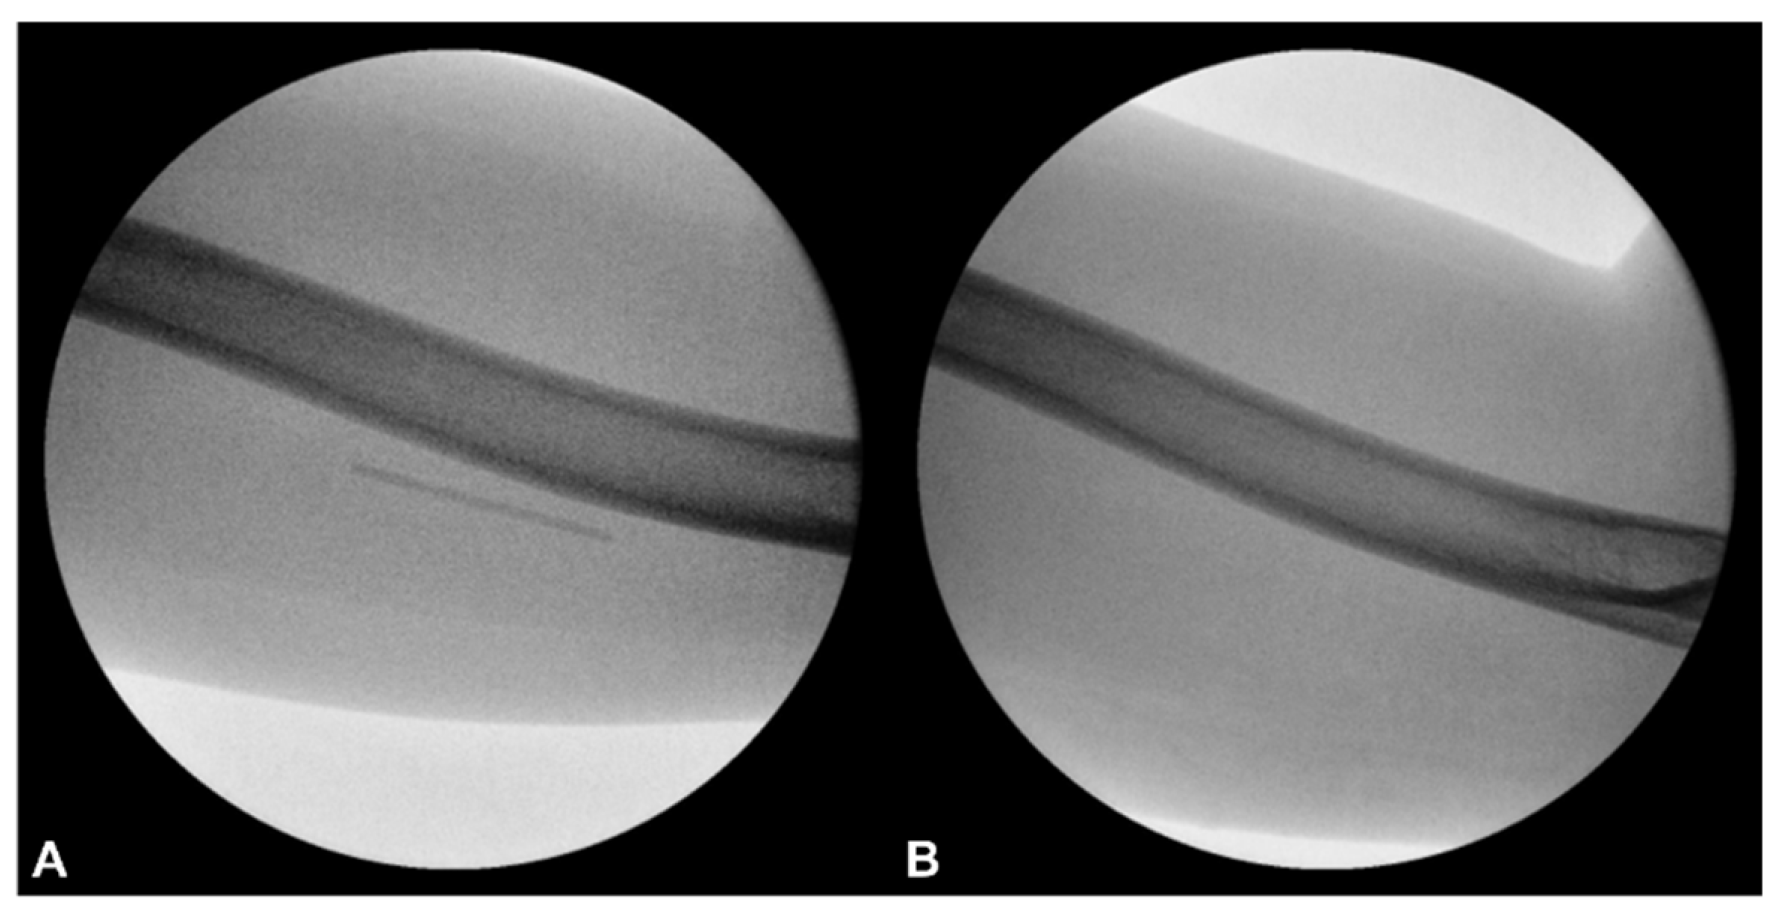

Figure 9. C-arm fluoroscopy images demonstrating the position of the Implanon® device before and after removal. (A) Pre-procedural image shows a linear radiopaque structure consistent with the retained implant in the medial arm. (B) The post-procedural image confirms complete removal, with no residual radiopaque material visible at the previously identified location.

Plain radiography of the left arm revealed no bony deformities or structural abnormalities accounting for her neurological symptoms. However, imaging demonstrated a linear radiopaque structure consistent with the residual Implanon device in the medial aspect of the arm (Figure 3).

Figure 3. Plain radiograph of the left arm showing a linear radiopaque structure consistent with the retained Implanon® device. No bony deformities or structural abnormalities were noted that could account for her neurological symptoms.

The entire 4-cm Implanon rod segment was removed intact (Figure 7). No additional incisions or surgical dissections were required. Hemostasis was achieved via manual compression, and the wound was approximated with adhesive strips. The patient tolerated the procedure well without any immediate complications. Complete removal of the implant was confirmed by concurrent C-arm fluoroscopy and US imaging (Figure 8 and Figure 9). Notably, the patient reported immediate substantial symptom relief, with pain severity decreasing to NPRS 2/10 (80% reduction). The entire procedure—including the intial removal attempt, US-guided HD, second attempt, further US-guided HD, percutaneous 25G needle stabilization, and final retrieval—was completed within two hours. Postprocedural monitoring for one hour revealed fluctuations in pain scores. A long-arm splint maintaining elbow extension was applied. Prophylactic antibiotics and one-day NSAID therapy were prescribed due to repeated wound manipulation and local inflammation. The patient was discharged home on the same day.